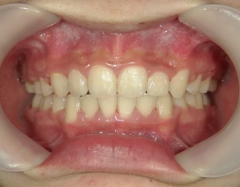

矯正歯科 治療後矯正歯科 全顎ワイヤー矯正 治療後矯正歯科(全顎ワイヤー矯正)治療後

矯正歯科 治療後

no.18_2196_治療後_右.jpgno.18_2196_治療後_正面.jpgno.18_2196_治療後_左.jpg